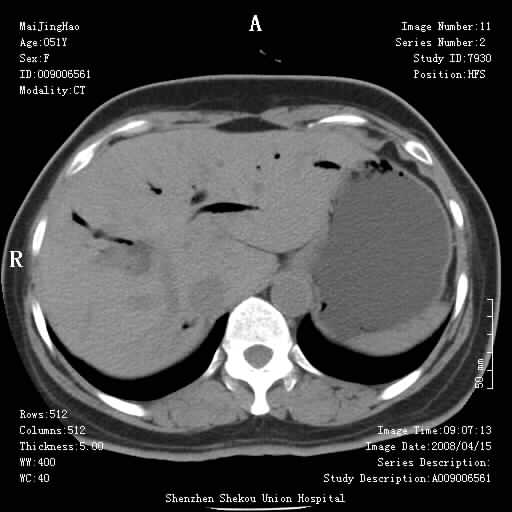

以下是引用余辉在2008-4-26 8:55:00的发言:[br]患者有结石史,此次腹痛4小时,胆总管全程扩张,应有胆总管末端梗阻,此次仍考虑胆结石症,积气不外两种原因,一种是结石下移时肠道内气体逸入,其次为产气菌感染。(倒数第三幅图像于扩张之胆总管末端似可见稍高密度影,考虑为结石影)

以下是引用yangyudong333在2008-4-26 6:17:00的发言:[br]1胆系感染,可能为金葡菌感染,2考虑有化脓性胆管炎致胆总管扩张,3胰头部增大,建议做增强

以下是引用听蝉观竹在2008-4-26 11:41:00的发言:[br]胆道手术分两种情况:[br]1、如果仅仅做胆囊切除手术,肝内胆管不会积气,只会出现胆总管代偿扩张,因为奥迪氏括约肌依然功能正常胆道与外界并不相通;[br][br]2、胆囊切除+胆总管空肠吻合手术(即roux-y式),则肝内胆管会出现积气,只是因为胆管与小肠相通,气体来源于小肠。这是临床十分常见的手术。[br][br]这个病例应该是胆囊切除+胆总管空肠吻合手术,是正常手术后表现,并不是胆道感染的表现。

以下是引用宇宙ct在2008-4-26 10:43:00的发言:[br][br] 胆囊切除术后胆管常因代偿而出现扩张,肝内胆管也经常会出现积气征象;胰头强化后再诊断。 [br] [br]

以下是引用听蝉观竹在2008-4-27 10:10:00的发言:[br]关于胰头大小问题有几种测量方法和正常值:[br][br]1、直量法:横径<4cm;[br]2、胰头横径与相邻层面椎体横径的比值为二分之一,超过椎体横径就提示胰头增大;[br]3、正常组成年人肠系膜上动、静脉水平夹角正常值范围为4.9°~34.7°大于35°提示胰头增大。[br][br]上述方法只是一种具体的判断,是“量”的评估,更重要的是“质”的评估:一是观察边缘是否光滑,有无局部隆起,有无分叶;二是观察密度(增强,尤其在动脉期和门脉期)是否均匀。[br][br]所以对于胰头是否有异常不仅仅是是目测可以解决问题的,不要轻易就说“胰头增大”。还有一个问题就是测量胰头应该在增强ct上进行,这样可以避免将血管测量进去。[br][br]为什么啰嗦讲怎么多,因为我们实际工作中同样存在影像科医生和临床医生动不动就说胰头增大,说是胰头癌。大家看看是不是这种情况?[br][br] 我个人观点-----本病例的胰头不增大。[br][br][本贴已被 听蝉观竹 于 2008-4-27 10:12:41 修改过]